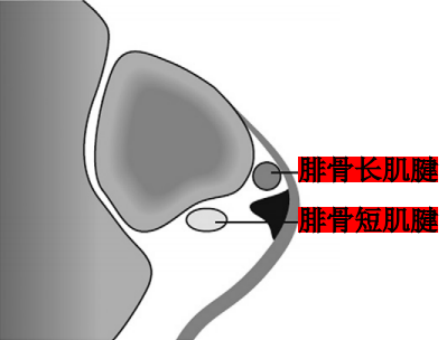

Ecket和Davis根据73例手术患者的术中观察发现并无腓骨上支持带的撕裂,他们将患者分为3型:

I型:最常见(51%),腓骨上支持带(SPR)和骨膜仍保持联系,骨膜从外踝上撕脱,腓骨肌腱滑向前方使骨膜和外踝分离。

Ⅱ型:(33%)纤维软骨脊连同腓骨上支持带(SPR)一起和外踝分离,腓骨肌腱向前脱位。

Ⅲ型:(16%)纤维软骨脊连同部分外踝骨质和腓骨上支持带(SPR)一起与外踝分离,肌腱脱位至骨折块下方。

IV型:Oden1987年在此基础上外,还有少见的第IV型,表现为腓骨上支持带(SPR)的完全撕脱或断裂,并且肌腱移位于支持带的外表面。

Raikin等学者提出将腓骨沟内腱鞘内半脱位不伴有腓骨上支持带损伤划为腓骨脱位的亚系。这些腱鞘内半脱位共有两型:

A型:腓骨肌腱无撕裂,肌腱暂时换位;

B型:腓骨短肌存在纵向撕裂,腓骨长肌腱自撕裂处半脱位。